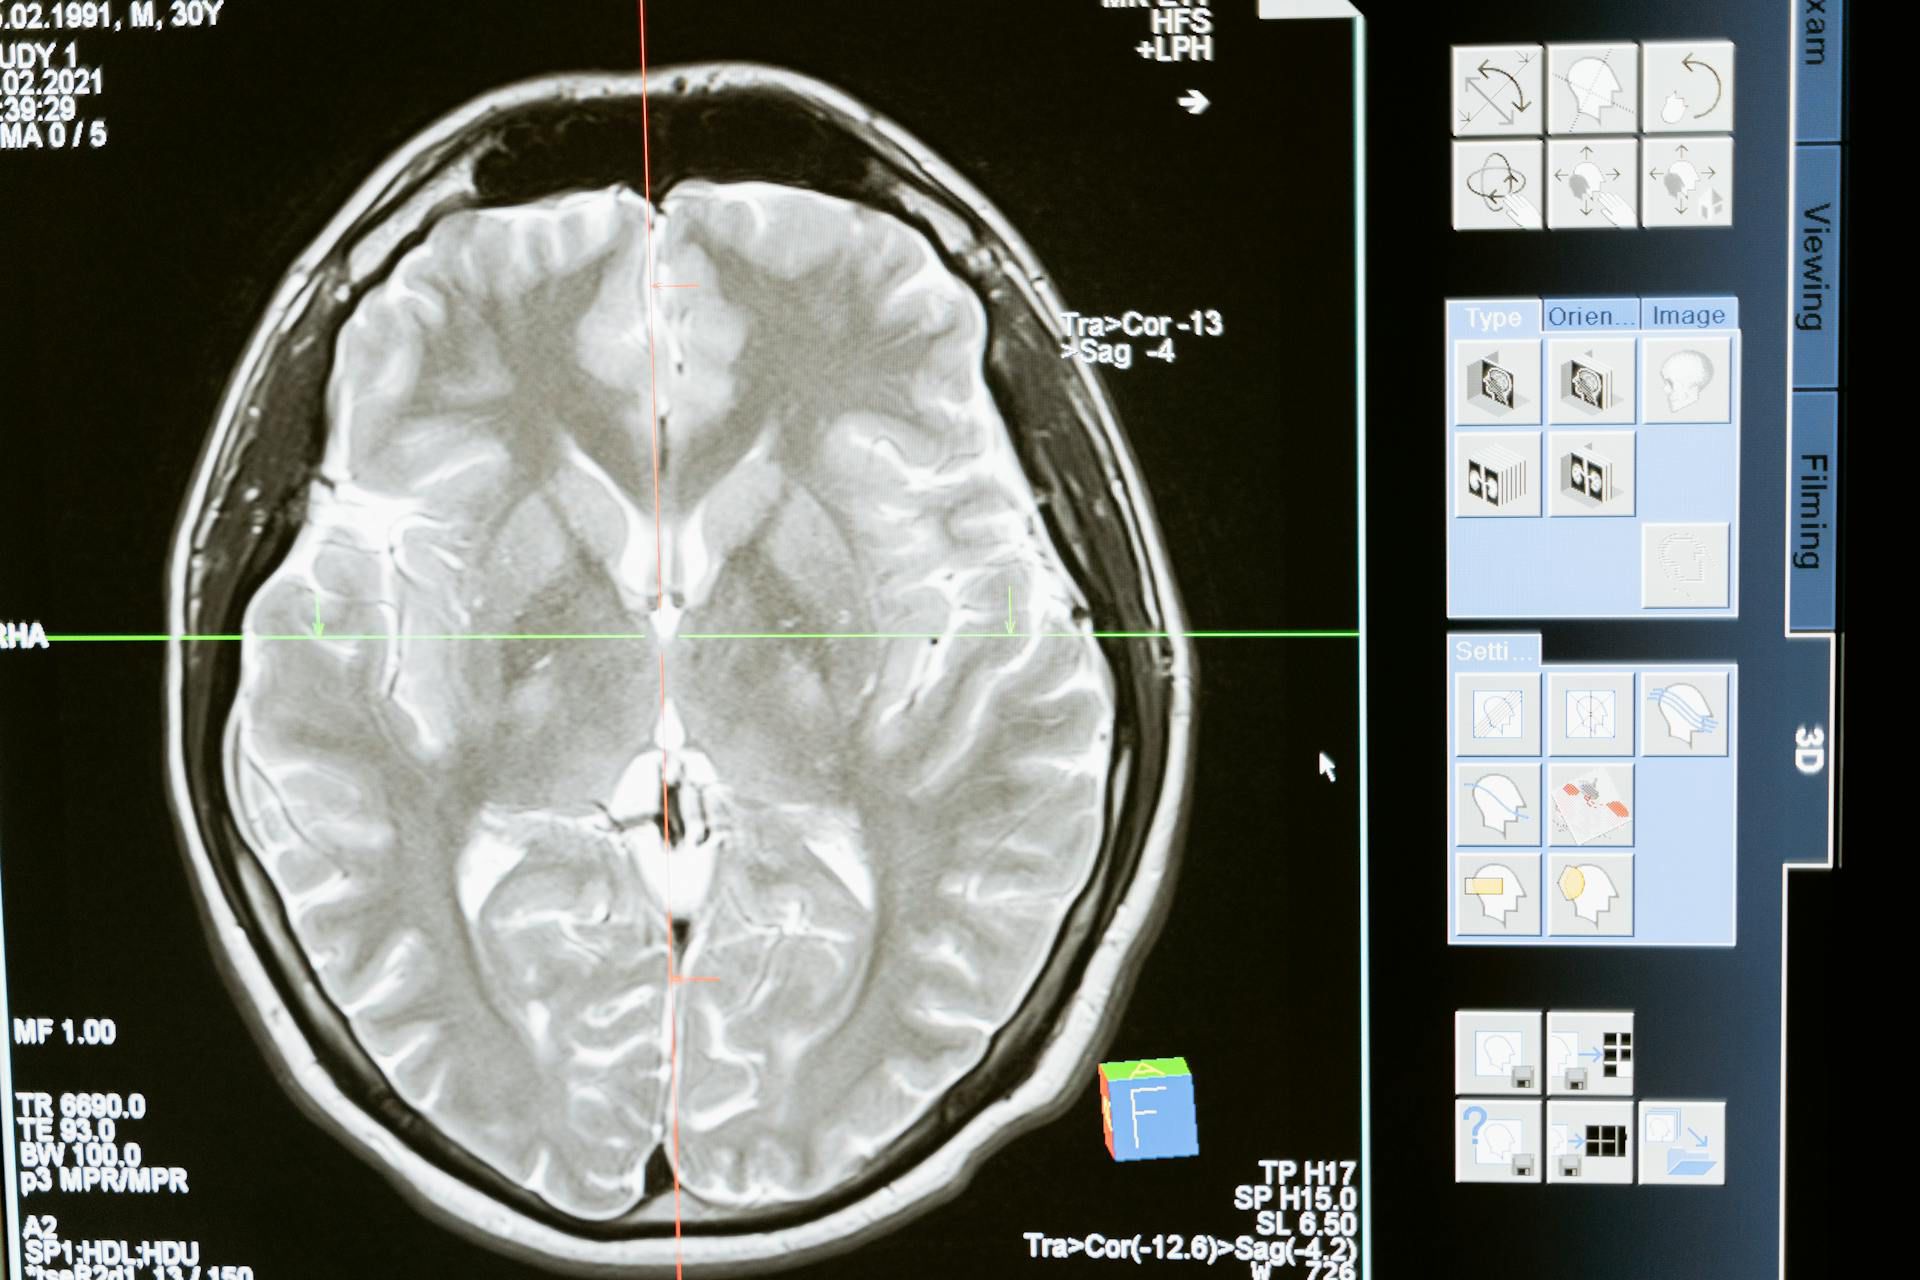

Procedendo dal basso verso l’alto, abbiamo riconosciuto il tronco encefalico, responsabile delle funzioni vitali come la respirazione e il battito cardiaco, seguito dal cervelletto, dove si distingue chiaramente la materia bianca interna e la materia grigia esterna.

Più in alto si trovano il diencefalo, suddiviso in talamo e ipotalamo, il corpo calloso, che collega i due emisferi, e infine la corteccia cerebrale, riccamente solcata da circonvoluzioni.

Durante l’osservazione, abbiamo individuato il solco di Rolando, che separa il lobo frontale da quello parietale, e la scissura di Silvio, che divide il lobo frontale da quello temporale. Queste caratteristiche, comuni anche al cervello umano, dimostrano come la struttura di base sia conservata tra mammiferi diversi.

Infine, sezionando un emisfero, abbiamo osservato la materia grigia nella parte esterna della corteccia, sede dei corpi cellulari dei neuroni, e la materia bianca all’interno, formata da fibre nervose che collegano le diverse aree cerebrali.